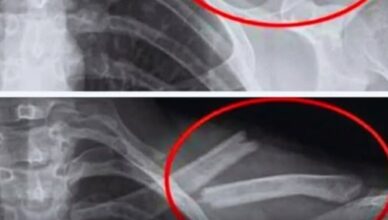

Ви коли-небудь відчували біль у ногах без видимої причини? Крихкі кістки чи нічні судоми? Що робити, якщо ваше тіло намагається послати вам сигнал?